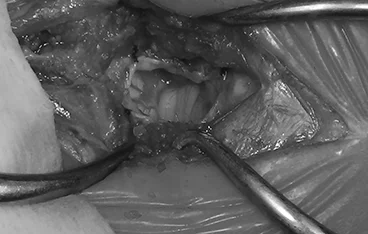

• 뇌종양